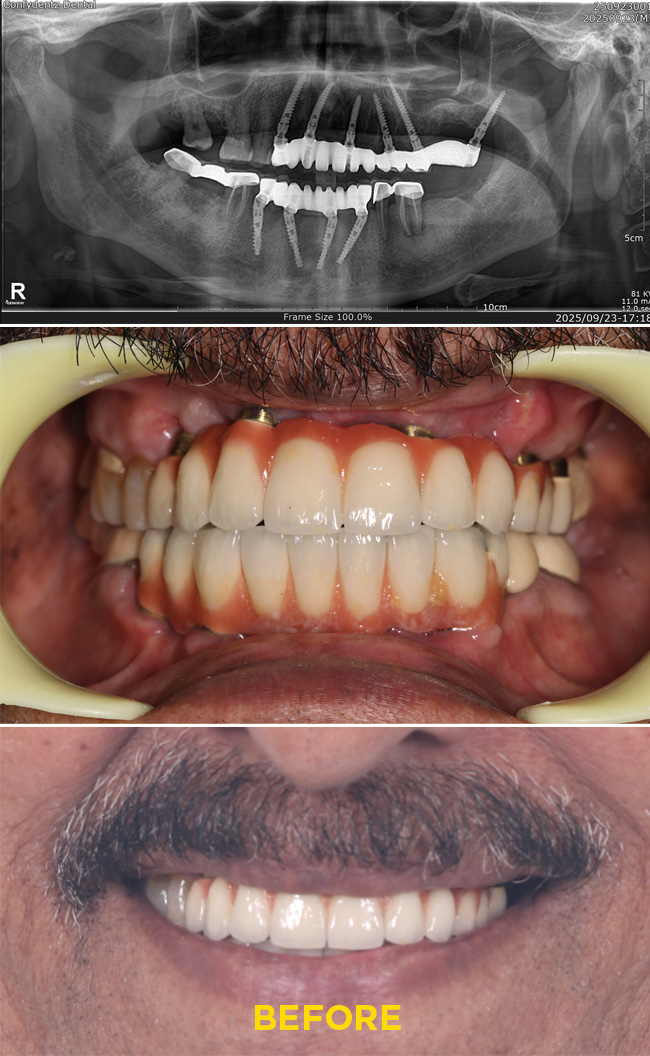

Case - 1